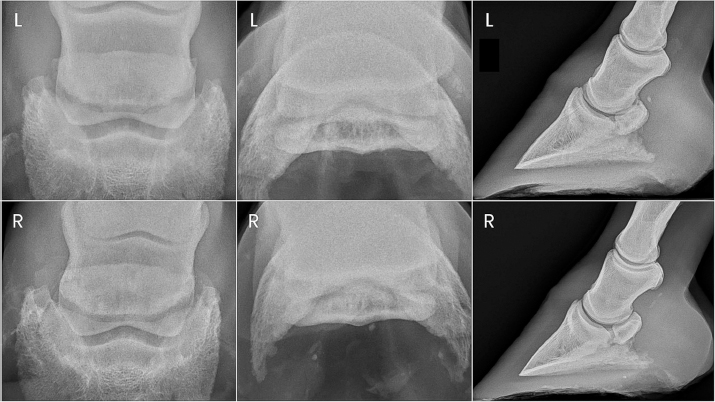

Fig. 1. Preoperative radiographs of the digits of horse 1.

Two years after donation, the gelding had progressed to displaying a grade 4/5 left forelimb lameness. This lameness was eliminated with diagnostic anesthesia of the left palmar digital nerves at the level of the proximal interphalangeal joint and replaced by a grade 4/5 right forelimb lameness. The right forelimb lameness was then eliminated with diagnostic anesthesia of the right palmar digital nerves in a similar fashion. PDN was performed as a salvage procedure to maintain pasture soundness. Abnormalities noted on the immediate preoperative radiographs included severe navicular bone degeneration bilaterally, osteoarthritis of the proximal and DIPJs bilaterally, and a focal area of mineralization in the area of the left DDF tendon just proximal to the navicular bone (Fig. 1).